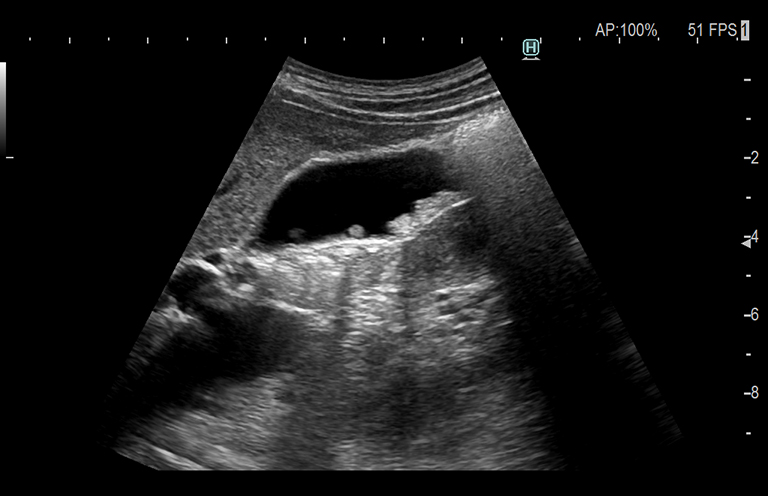

Aplicación: Abdomen

Función/análisis: Modo B

Comentarios: Vesícula biliar